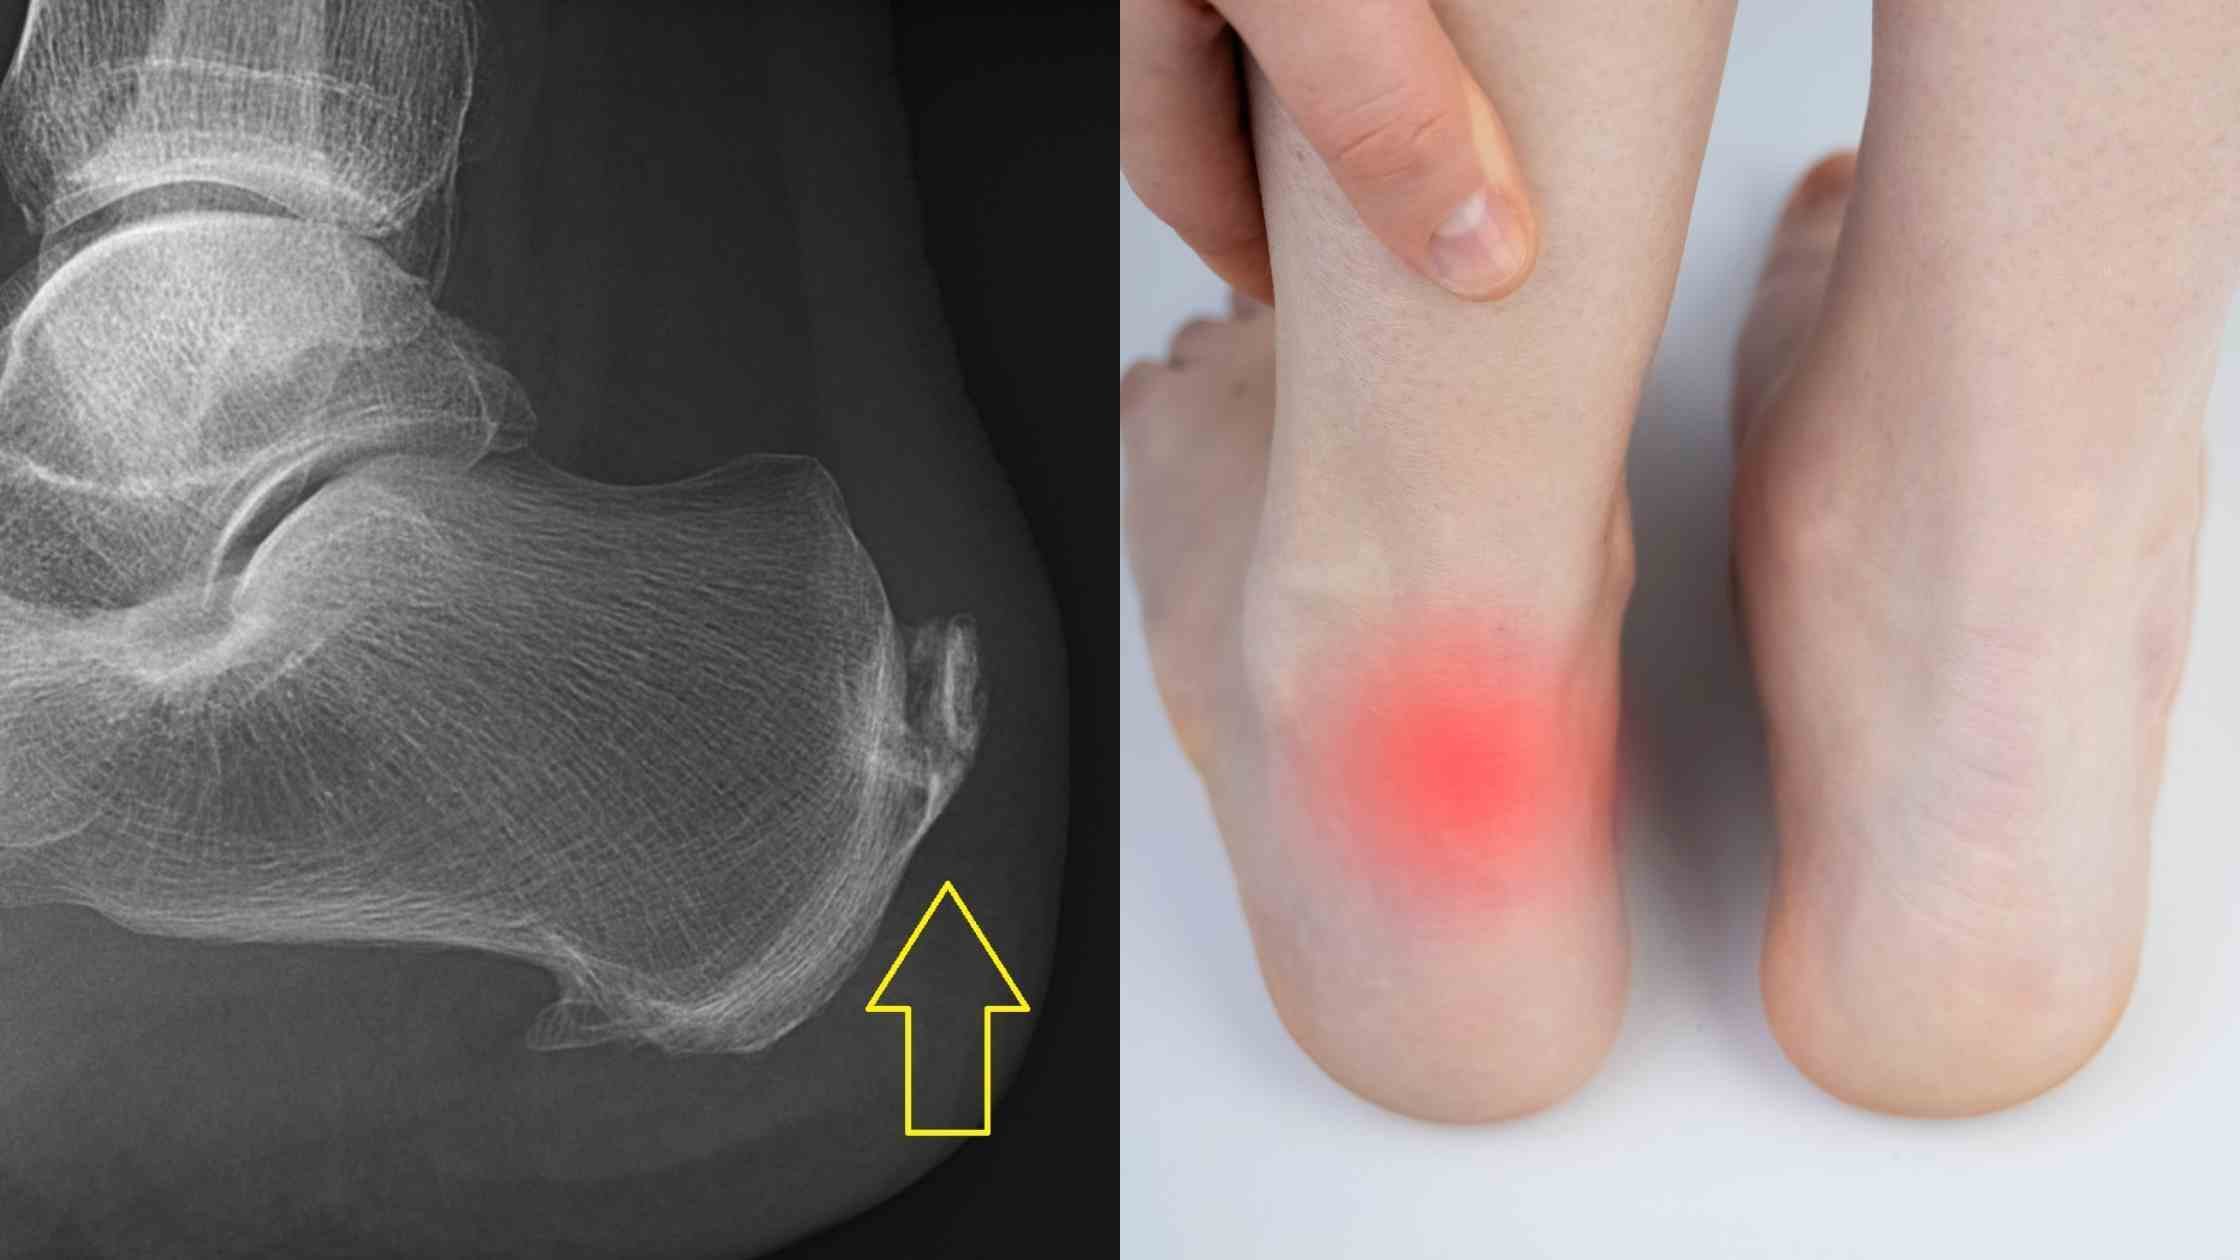

Achilles Insertional Calcific Tendinopathy (ACIT) is a condition caused by the continual stressful wear and tear of the tendon at the insertion in the heel, resulting in bone spurs over the years. ACIT can cause heel pain in both active and sedentary people and your condition may be aggravated by repetitive strain, sudden increased intensity of exercise, tight calf muscles or faulty footwear.

Symptoms that you could identify are stiffness, constant swelling, severe pain that worsens in the morning and with activity or a day after exercising, thickening of the tendon and bone spurs, or calcium deposits.